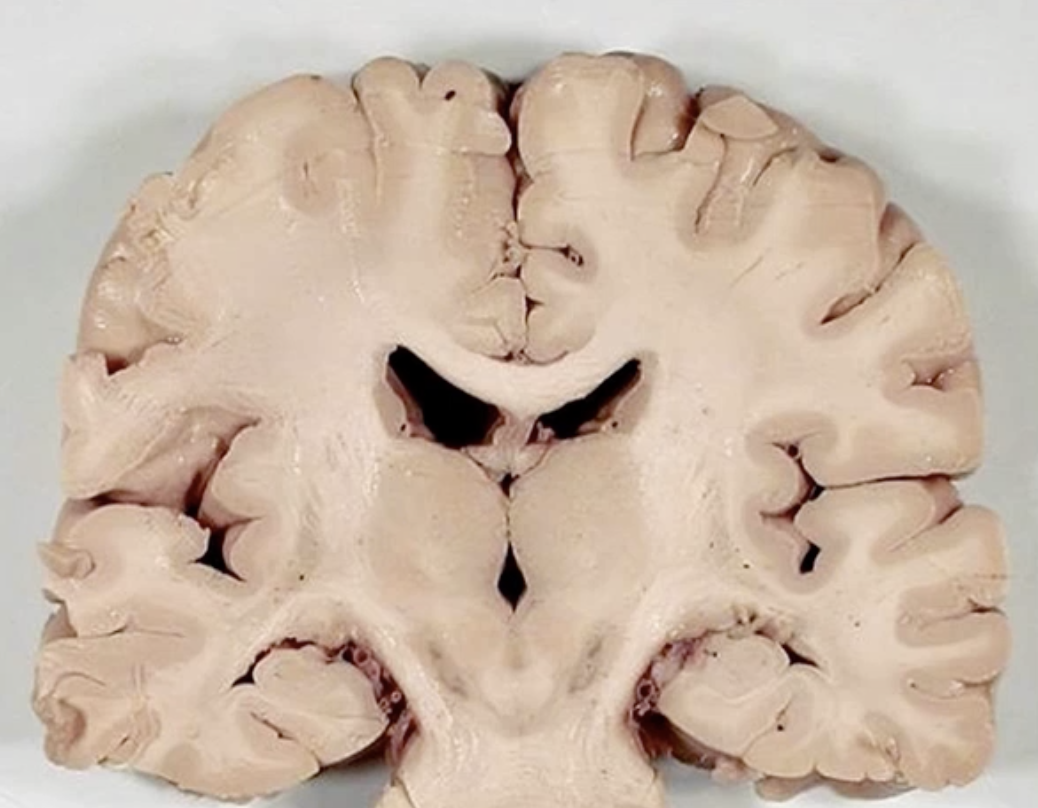

Diag?

Huntingtons